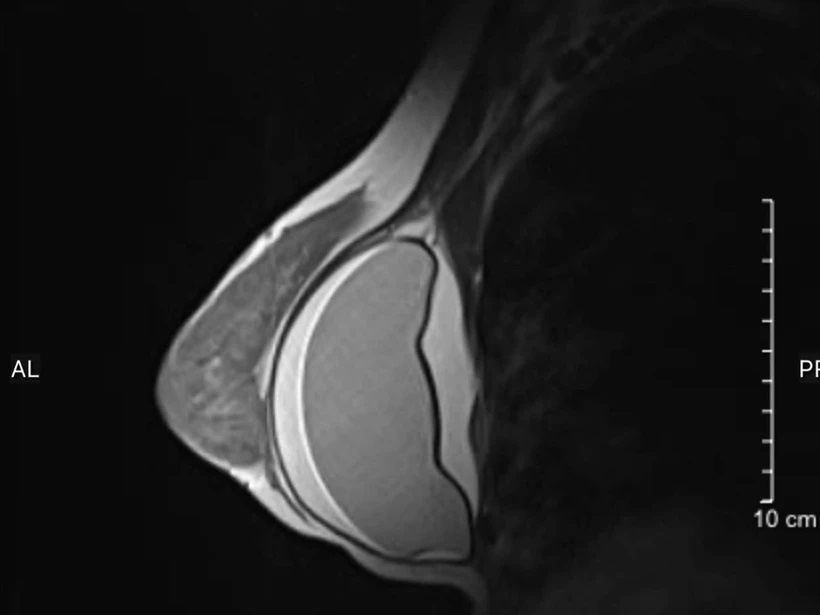

Các kết quả siêu âm, chụp MRI ghi nhận túi ngực bên trái của bệnh nhân bị vỡ, vùng khoang ngực xung quanh túi ngực có nhiều dịch (dày khoảng 2 cm).

Trường hợp còn lại là một phụ nữ 55 tuổi, ở Hà Nội, đặt túi ngực từ năm 2010, cách đây 14 năm. Ngày 22/4, người phụ nữ tới Bệnh viện Đại học Y Hà Nội thăm khám tổng quát. Kết quả siêu âm cũng như chụp MRI cho thấy hình ảnh túi ngực bên trái đã vỡ.

Hình ảnh chụp MRI ngực của một bệnh nhân tại Bệnh viện Đại học Y Hà Nội. Ảnh: BVCC.